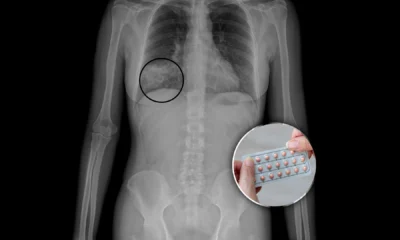

Las mujeres tienen una capacidad enorme para resistir el dolor, y por eso muchas veces confunden cólicos con algo mucho más grave. Ayúdame a que esta...